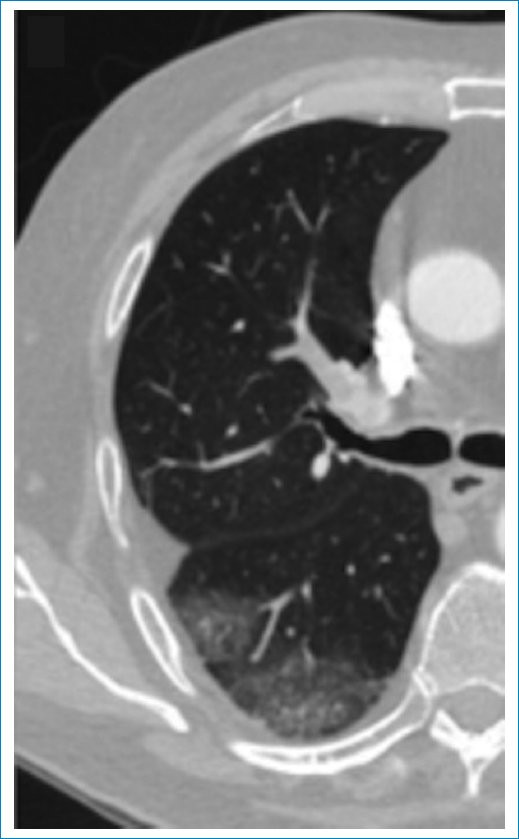

- Opacidad periférica con radiolucencia central: con una especificidad del 98% y sensibilidad del 46%, es el signo más específico para IP5. Consiste en una opacidad consolidativa periférica que contiene áreas de radiolucencia central. Dicho hallazgo se debe principalmente al llenado alveolar con contenido hemático, que se traduce en áreas de vidrio esmerilado central. También es considerada secundaria a necrosis central, con una reacción inflamatoria alrededor, opacidad consolidativa periférica, donde las zonas más excéntricas pueden representar un tejido viable (Fig. 1)6.

La radiolucencia central en una consolidación periférica subpleural es un signo tomográfico altamente específico para IP.